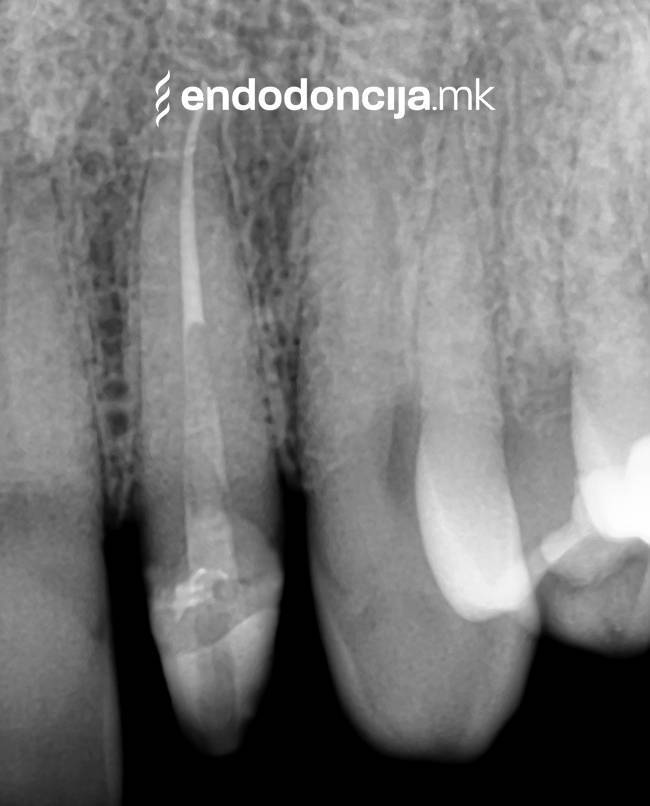

Σε περίπτωση ανανέωσης της θεραπείας του ριζικού καναλιού (αναθεώρηση) παλιά γεμίσματα ρίζας που δεν ήταν επιτυχημένα και ως εκ τούτου ήταν η αιτία φλεγμονών και πόνου, μπορούν να αφαιρεθούν και να ανανεωθούν εξειδικευμένα. Αυτή η θεραπεία εξαλείφει τις φλεγμονές στην περιοχή της ρίζας και καθίσταται δυνατή η πλήρης ανάρρωση.

Κατά τη διάρκεια προηγούμενων θεραπειών, το δόντι μπορεί όχι μόνο να έχει αποδυναμωθεί από τη μηχανική επεξεργασία του ριζικού σωλήνα αλλά και από τη στερέωση και την αγκύρωση ενός ρίζα. Όταν αναθεωρείται η επεξεργασία ενός ριζικού καναλιού, αυτοί οι πείροι πρέπει να αφαιρούνται όσο το δυνατόν πιο προσεκτικά για να διατηρούν σημαντική ουσία των δοντιών.